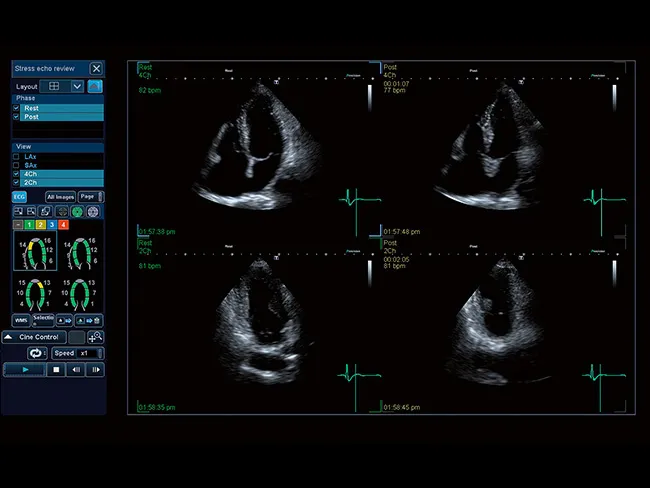

Поддерживая стандартные и определяемые пользователем протоколы как для физического, так и для фармакологического воздействия, Aplio предлагает комплексный пакет для быстрой и точной оценки движения стенки.